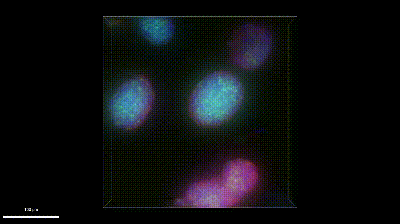

假小細(xì)胞(胰島β細(xì)胞)-THUNDER Imager 3D 細(xì)胞培養(yǎng)儀

生長為假小體(胰島β細(xì)胞)的 MIN6 細(xì)胞。DAPI(藍(lán)色)、胰島素(Alexa488,綠色)、膜受體(Alexa594,紅色)、類磷脂質(zhì)蛋白(Alexa647,白色)。樣本由德國巴特諾海姆馬克斯-普朗克心肺研究所 Rémy Bonnavion 博士提供。